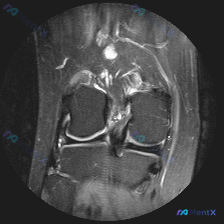

拿到这份病例和影像,先整理一下所有信息,再梳理思路: 一、核心临床问题 本次提出的核心疑问是:判断是否存在半月板异常 二、现有影像学发现(膝关节MRI T2序列冠状位单层面) 我先把所有客观发现整理出来: 1. 骨骼与关节软骨:股骨远端、胫骨近端骨皮质连续,无骨折;骨髓信号均匀,无明显水肿/硬化;关...